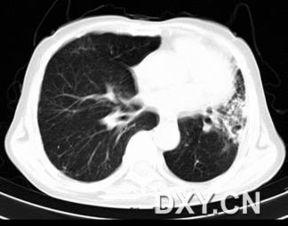

观察镜子中的肺部运动。正常情况下,你的肺部应该随着呼吸上下移动。如果肺部运动异常,比如一侧运动明显减弱,那么可能需要进一步检查。